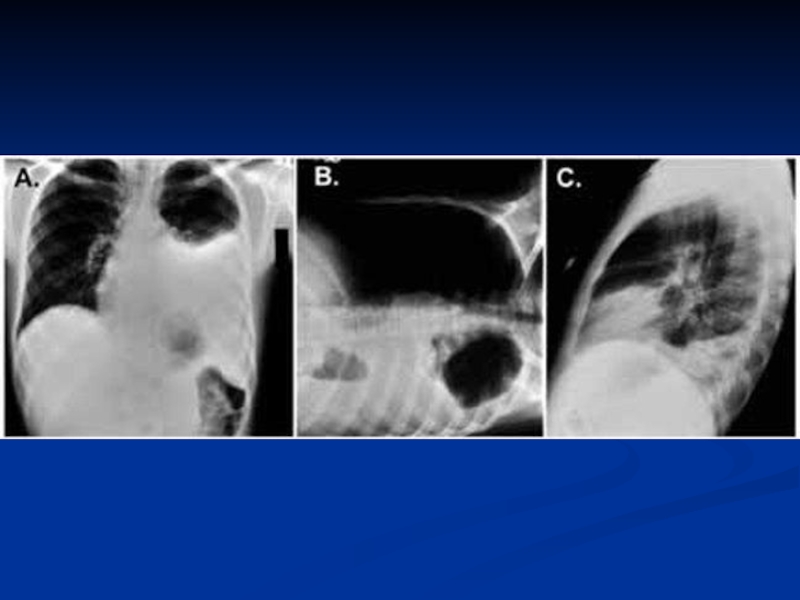

рентгенограмма: инфильтраты легочной ткани, чаще с обеих

сторон; усиление легочного рисунка в перифокальных участках.

рентгенограмма: инфильтраты легочной ткани, усиление легочного рисунка в перифокальных участках.